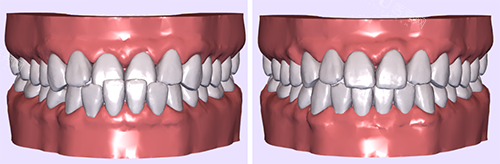

除了常见的儿童牙齿治疗项目外,郑州快乐蜗牛口腔还提供齐全的口腔服务。包括儿童牙齿预防保健,如涂氟、窝沟封闭等,帮助孩子预防龋齿的发生;早期牙齿矫正,针对一些有牙齿不齐倾向的孩子,进行早期干预和矫正,避免问题进一步恶化;以及口腔健康教育,通过生动有趣的方式向孩子和家长传授正确的口腔护理知识,培养孩子良好的口腔卫生习惯。